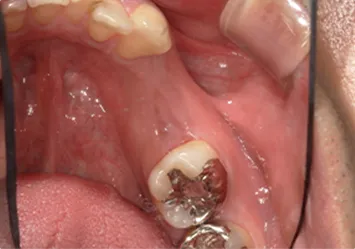

治療前

治療前写真 恵比寿南DENTAL

治療後

治療後写真 恵比寿南DENTAL

施術内容

【20代女性】

右下7番の歯根破折してしまい保存不可能となってしまった歯を抜歯し、インプラント埋入

治療期間

5ヶ月

リスク

術中の不可抗力によるトラブル(出血など)、術後注意事項を守らないことによる疼痛、感染、上部構造装着後口腔内清掃を怠ったことによるインプラント周囲組織の炎症

副作用

治療後の口腔内清掃、及びメインテナンスを怠ったことによるインプラント周囲粘膜炎またはインプラント周囲炎

費用

インプラント埋入:30万円

ジルコニアクラウン:12万円